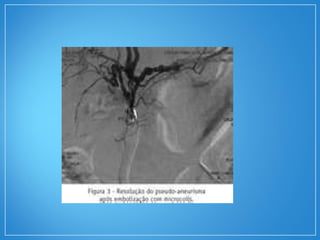

A angiografia seletiva da região abdominal

(tronco celíaco e artérias renais) pode evidenciar

a presença de estenoses irregulares e de

múltiplos microaneurismas característicos da

PAN.

• O diagnósticoda PAN depende da evidência histológica de vasculite. A biopsia de órgãos clinicamente afetados, como nervos periféricos, testículo e pele, tem uma sensibilidade de 65%. A angiografia seletiva da região abdominal (tronco celíaco e artérias renais) pode evidenciar a presença de estenoses irregulares e de múltiplos microaneurismas característicos da PAN.